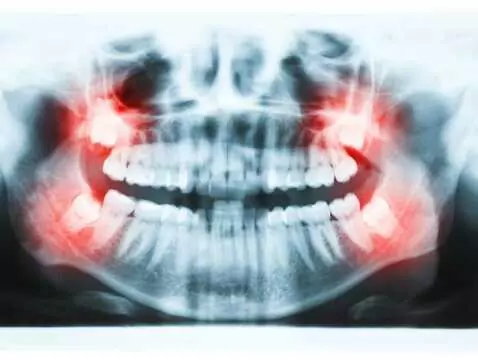

Wenn die Weisheitszähne durchbrechen, ist dies meist mit Schmerzen verbunden. Die Unannehmlichkeiten und das unangenehme Gefühl, wenn die Achter herauskommen, können von selbst abklingen, aber in...